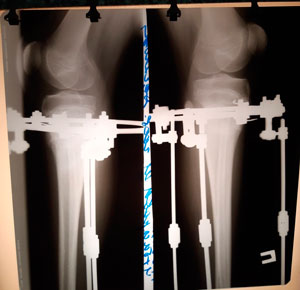

перед крутками

IMG_2605-20-04-19-02-51.JPG

5 - ый день круток

IMG_2848-30-04-19-04-45.JPG